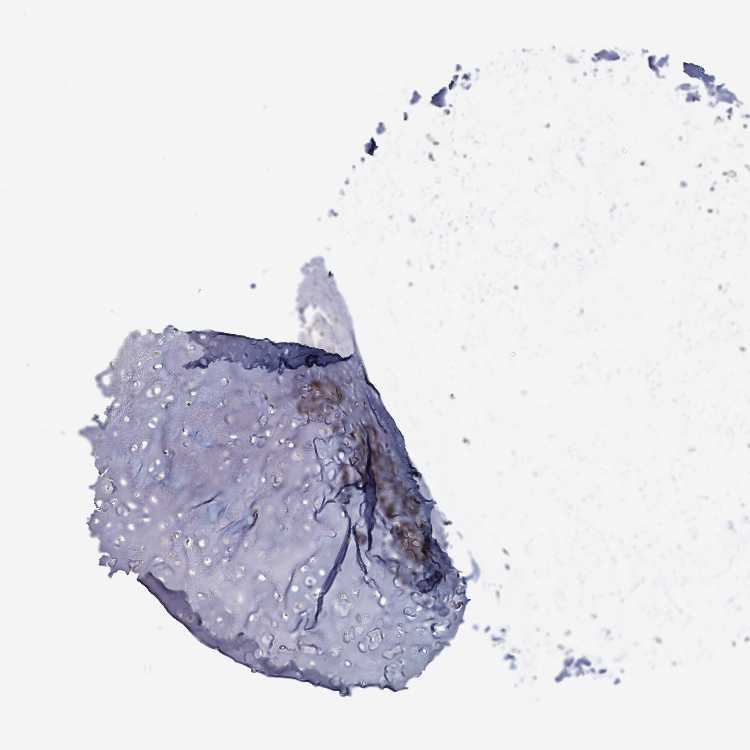

SOFT TISSUE 1 - Antibody stainingi

Antibody staining in the annotated cell types in the current human tissue is reported as not detected, low, medium, or high, based on conventional immunohistochemistry profiling in selected tissues. This score is based on the combination of the staining intensity and fraction of stained cells.

Each image is clickable and will lead to virtual microscopy that enables deeper exploration of all samples and also displays staining intensity scores, fraction scores and subcellular localization as well as patient and tissue information for each sample.

Antibody HPA050724

Chondrocytes Low